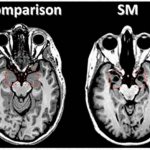

Как вспомогательный диагностический критерий поражения головного мозга и оболочек у 21 (17,5%) больного были использованы КТ и МРТ: очаги демиелинизации были выявлены у 13 (61,9%) больных, ликворные кисты — у 10 (47,6%), смещение срединных структур — у 5 (23,8), снижение плотности вещества мозга — у 17 (81%), утолщение мозговых оболочек — у 2 (9,5%), нарушение ликвородинамики — у 18 (85,7%).